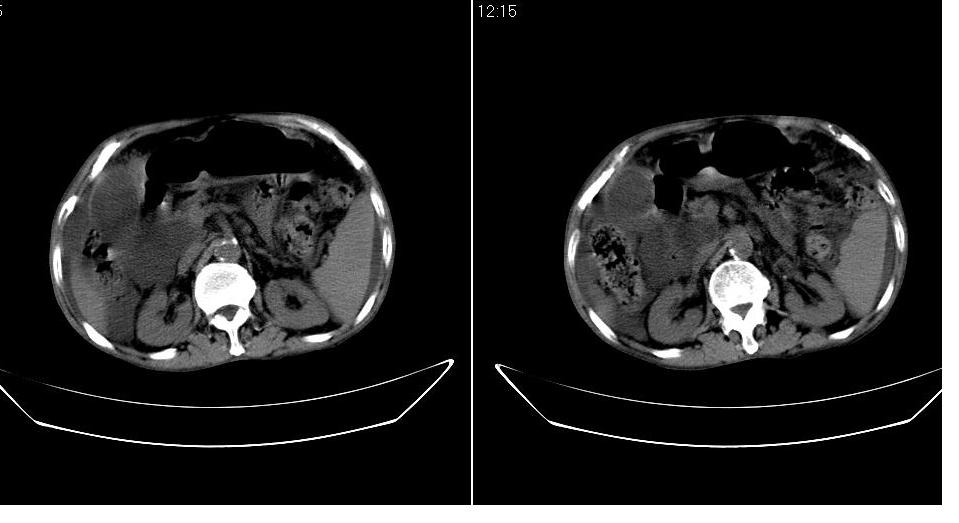

男 78岁,全身黄染,病人家属拒绝增强。

胆总管下端梗阻(原因待查)伴肝内外胆管扩张、胆囊积水。

肝周 脾周 胆囊窝内明显积液,胆囊扩大,胆囊壁模糊,肝内胆管扩张。考虑;胆囊癌周边侵润伴腹水。

1、梗阻性黄疸(胆总管下段病变或十二指肠病变)。

2、胆囊炎,腹水。

3、肝内钙化灶(寄生虫?)。